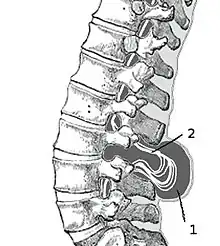

(1) Sac extern cu lichid cefalorahidian(LCR)

(2) Măduva spinării herniată și prinsă între vertebre

Meningocelul este forma cea mai rară a spinei bifide, se mai numește și chist meningeal. Meningocelul afectează meningele(membrana care acoperă măduva spinării) și care iese(herniază) printr-o breșă, formând un mic sac, care se numește meningocel (în limba greacă meminx=membrană, kele=umflătură).

În cazul meningocelului posterior vertebra se dezvoltă normal, cu toate acestea, meningele herniază între vertebre. Dacă sistemul nervos rămâne neafectat, sunt șanse mici ca bolnavul să prezinte probleme de sănătate pe termen lung.

Mielomeningocel

Mielomeningocelul este forma cea mai frecventă și severă de spină bifidă, cu complicațiile cele mai grave.[5] Mielomeningocelul apare atunci când meningele și măduva spinării ies prin spațiul intervertebral(herniază) sub forma unui sac. Spina bifidă cu mieloschizis este forma cea mai gravă a mielomeningocelului. La acest tip de afecțiune zona afectată este reprezentată de o masă de țesut nervos fără membrană de protecție, ceea ce expune bebelușii la infecții periculoase cum ar fi meningita.[6]